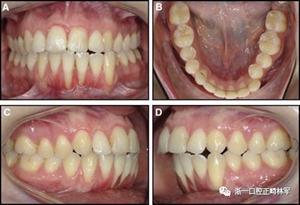

圖7.左右切牙扭矩不一致的柔性螺旋弓絲保持器:A,正面視圖; B,咬合面視圖。 下頜左側(cè)尖牙的唇側(cè)移位:C和D,頰面視圖(Anne-Marie Renkema博士提供)。